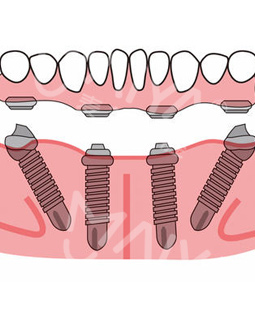

麦芽的博士专家团在看过我的片子后发现,我的牙齿由于长期对口腔疏于护理,牙周情况非常差,余牙有些松动,且牙槽骨萎缩严重,现存的骨量无法进行传统的种植牙手术,因此给我设计了“all-on-4”种牙技术的升级版本“all-on-5”,前期是要处理我的牙周问题,当天就给安排了洁牙,然后上药,等牙周恢复差不多就可以进行种植了!

但是打完麻药,躺在那里发现手术时一点感觉也没有,半口牙只种了5颗牙钉,而且不到一个小时,感觉自己就眯了一会就好了。麦芽的种植专家们手法特别棒,很稳。牙钉种好之后,没有立即戴牙冠,医生用硅橡胶取模,为我制作了临时牙冠,不过看到临时牙冠我就能想象到完全种好牙的样子了!然后,医生给我一个小卡片,上面记录了种牙后的注意事项,告诉我种完牙后自己维护也很重要。医生说要按时复诊,也会有专门的工作人员进行通知,不得不说麦芽在细节上真的很暖心。